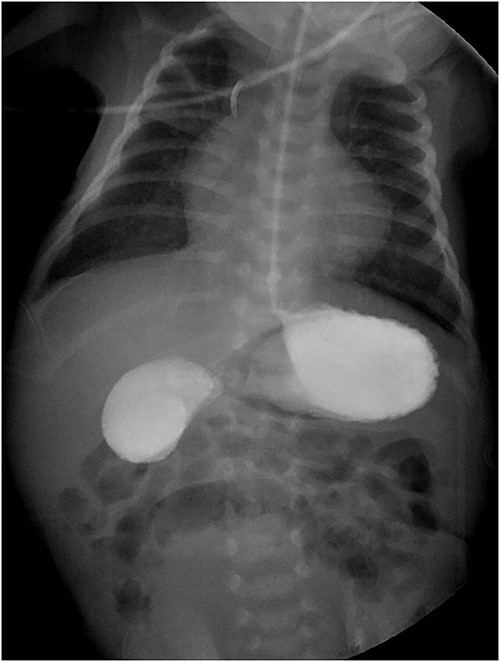

The gastroduodenal series showed data compatible with a duodenal membrane between the second and third portions of the duodenum (Fig. 1). Based on the above, exploratory laparotomy was scheduled, where in the transoperative period, the pancreas was found completely wrapping the second portion of the duodenum (Fig. 2A), so it was decided to perform a diamond-shaped-duodenoduodenostomy anastomosis (Fig. 2B–D), which was performed without eventualities. He continued his postoperative period in neonatal intensive care, where after 5 days with nasogastric tube and fasting, the nasogastric tube was removed, and the oral diet was well tolerated. The patient was reviewed 1 week after discharge for the removal of surgical stitches; this was done at 3 and 6 months also, with adequate development and growth.

Intraoperatively images. (A) AP is shown in the second portion of the duodenum. (B–D) Process of the diamond-shaped-duodenoduodenostomy anastomosis.